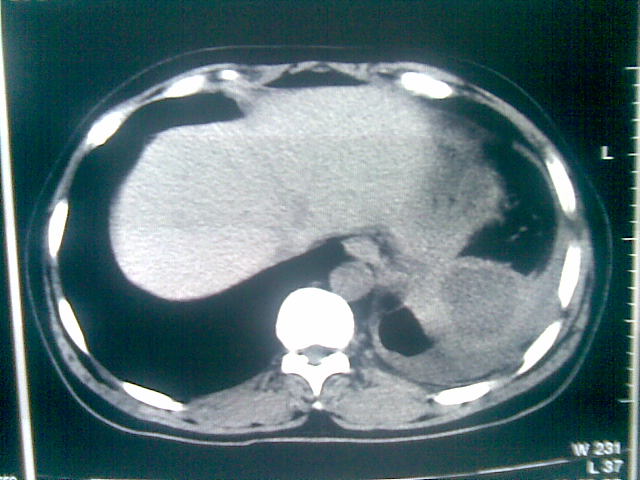

标题: CT23981:男,38岁阑尾炎术后透视胸腔积夜!做CT如下!积液包 [打印本页]

标题: CT23981:男,38岁阑尾炎术后透视胸腔积夜!做CT如下!积液包

可能与阑尾术后关系不太大,1.胸膜增厚粘连见少量气体。包裹脓气胸?左侧网膜囊脓肿?

.胸膜增厚粘连见少量气体。包裹脓气胸

左侧胸膜增厚、粘连+包裹液气胸。